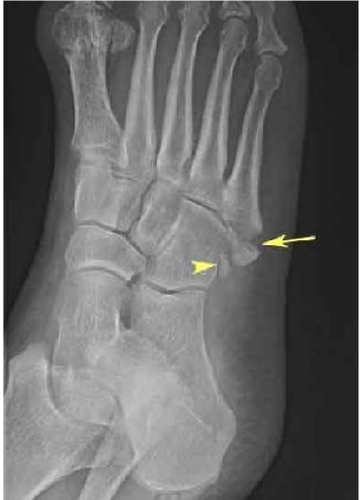

Communited fracture

Direct impact that shatters a bone into several fragments.